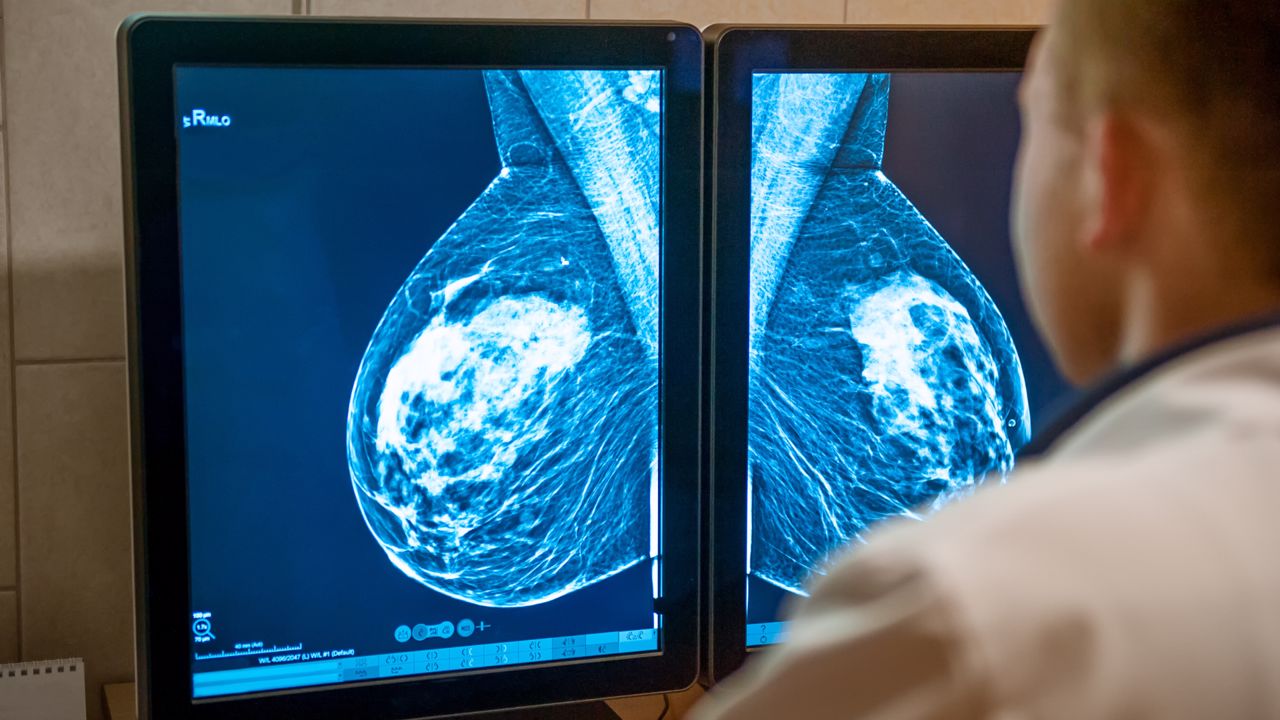

El método más eficaz en la actualidad para la detección precoz del cáncer de mama es la mamografía. La ecografía también puede ser un examen muy útil, sobre todo para las mujeres que aún son jóvenes.